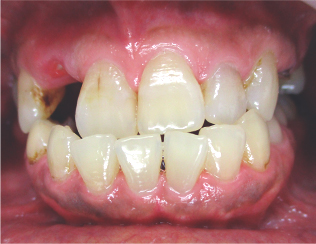

この方は歯並びもかなり悪く、虫歯も重度でした。

抜歯する歯もありましたがブリッジで治す事が出来ました。

1回目の治療時に仮歯を入れますのですぐに歯が入りますし、虫歯で欠けたりしている部分も無くなります。

当院のセラミック法でしたら歯並びも重度虫歯も一緒に治療が可能です。